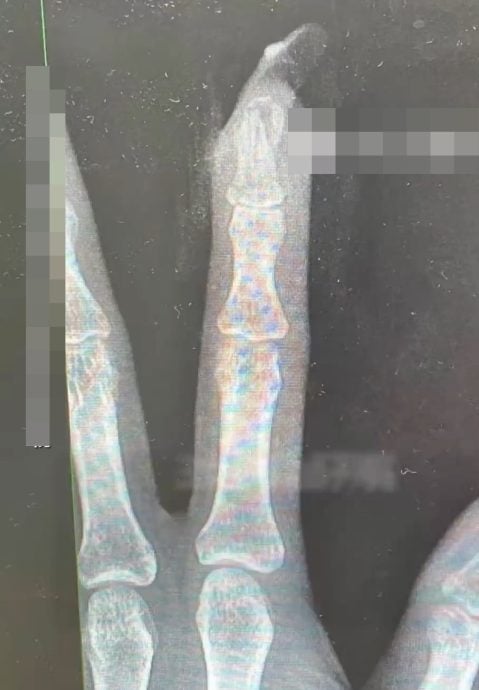

随后,王女士被紧急送往临平区中西医结合医院求医。接诊的骨科医生曹立在检查后发现,伤势远比想象中严重,不仅甲床严重破裂流血,甚至连指骨都出现了骨折情况。由于伤势涉及指甲断裂及甲床外露,必须通过手术进行修复。

曹医生指出,这起骨折意外的“祸首”正是那长长的甲片。由于延长甲增加了手指受力的杠杆长度,在跌倒触地时会产生更大的冲击力,如果当时没有美甲,伤势未必会如此严重。

所幸经过指骨骨折闭合复位内固定手术后,王女士目前恢复情况良好。专家借此提醒,女士在追求美甲效果时,应适度考虑指甲长度,以免在日常活动或突发意外中,让指尖艺术变成伤手利刃。